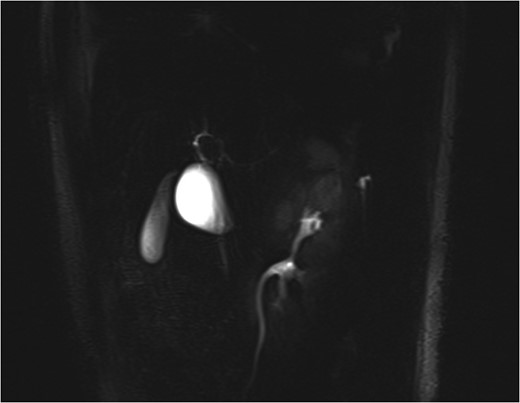

MRCP showing the cystic dilatation along the lateral wall of the bile duct mimicking a Type II choledochal cyst with GB seen separately.

Preoperative diagnosis of Type VI choledochal cyst is challenging. Ultrasound abdomen is a good screening investigation in these patients. The cyst appears hypoechoic and well demarcated. MRCP or multi-detector computed tomography can also suggest the diagnosis preoperatively. The most common diagnostic confusion on preoperative MRCP is with a Type II choledochal cyst due to its similar morphology. The definitive anatomy may be delineated by ERCP. This is seldom performed due to its invasive nature. However, in patients presenting with jaundice and features of biliary obstruction or suspicious malignancy, ERCP is a definitive investigation to aid in diagnosis. Tc99m HIDA scan can be helpful in defining the biliary origin of the cyst. In cysts with wide-based stalk and proximity to the CBD, intraoperative cholangiogram is a useful adjunct on table to define the biliary anatomy [8–10].